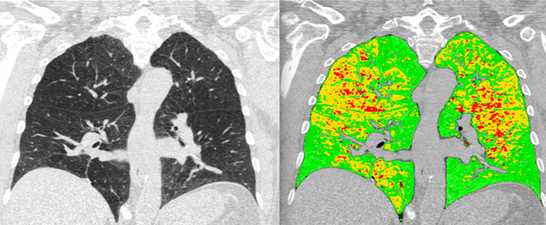

- Functional imaging of large and small airways

- Imaging of COPD and smoking-related disease